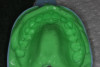

Fig 4. Preoperative mandibular impression made from VPS.

Figure 4